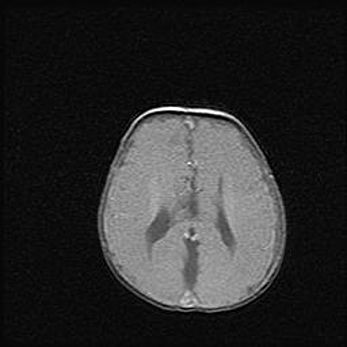

Открытая гидроцефалия.

Возраст: 6 месяцев 15 дней

Вес: 6200 г

Пол: женский

Окружность головы: 41 см

Срок гестации: 38 недель

Гидроцефалия головного мозга у новорожденных – это скопление избыточного количества цереброспинальной жидкости в головном мозге. Ее избыточное скопление в мозге приводит к патологическому расширению желудочков мозга (четырех полостей, расположенных в глубине белого вещества мозга, заполненных цереброспинальной жидкостью и связанных узкими проходами).

Открытый тип гидроцефалии (сообщающаяся) наблюдается тогда, когда нарушен механизм всасывания ликвора в системный кровоток. При этом типе причиной заболевания чаще всего является перенесенные ранее инфекции (например: менингит),  либо же наличие крови в субарахноидальном пространстве.